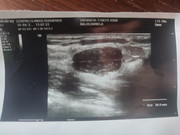

L'attesa si fa snervante ,sono riuscita(spero ) a caricare la foto dell' ecografia del del nodulo a margine netti del quale sto aspettando esito biopsia ....se fosse così gentile da darci un occhiata ...lo spero tanto .grazie ....

Probabilmente non servirà a niente ma non le ho detto che 6 anni fa ho terminato un allattamento durato 3 anni .

Forse dovresti scrivere anche il referto dell'ecografia.

Gliel'ho scritto qualche giorno fa ...